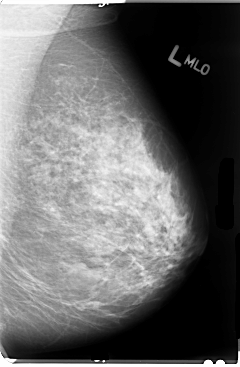

B_3036_1.LEFT_MLO

LEFT_MLO LINES 4760 PIXELS_PER_LINE 3120 BITS_PER_PIXEL 12 RESOLUTION 50 NON_OVERLAY